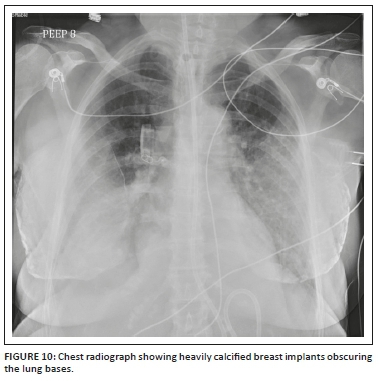

Medical devices and materials such as electrocardiogram (ECG) leads, ventilator tubing, syringes, clamps, temperature sensors, post-coronary artery bypass grafting (CABG) sternotomy wires, surgical clips, orthopaedic implants, gown snaps, etc. are commonly seen on CXRs. Because of its limited scope, we have not included cardiac devices in this article. However, there are other non-cardiac iatrogenic objects that can be seen on CXRs and these have been summarised in Table 2. Radiologists need to recognise them, be aware of their function and look for any related complications.